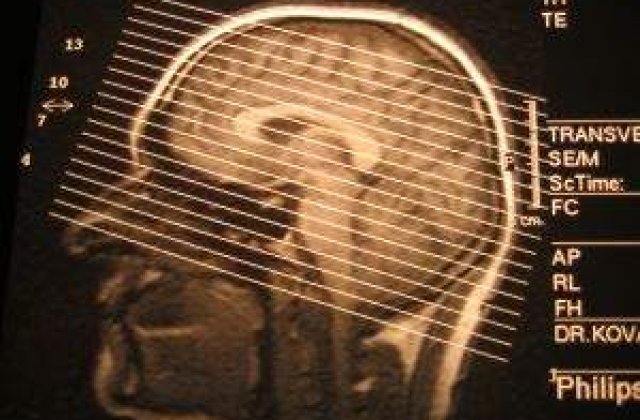

Potrivit medicilor, actorul a suferit o complicatie post-operatorie, acumuland in continuare lichid la creier dupa operatie de pe 21 mai.